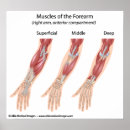

Muskeln des Unterarms, beschriftet Diagramm Poster

PreisCHF 71.25